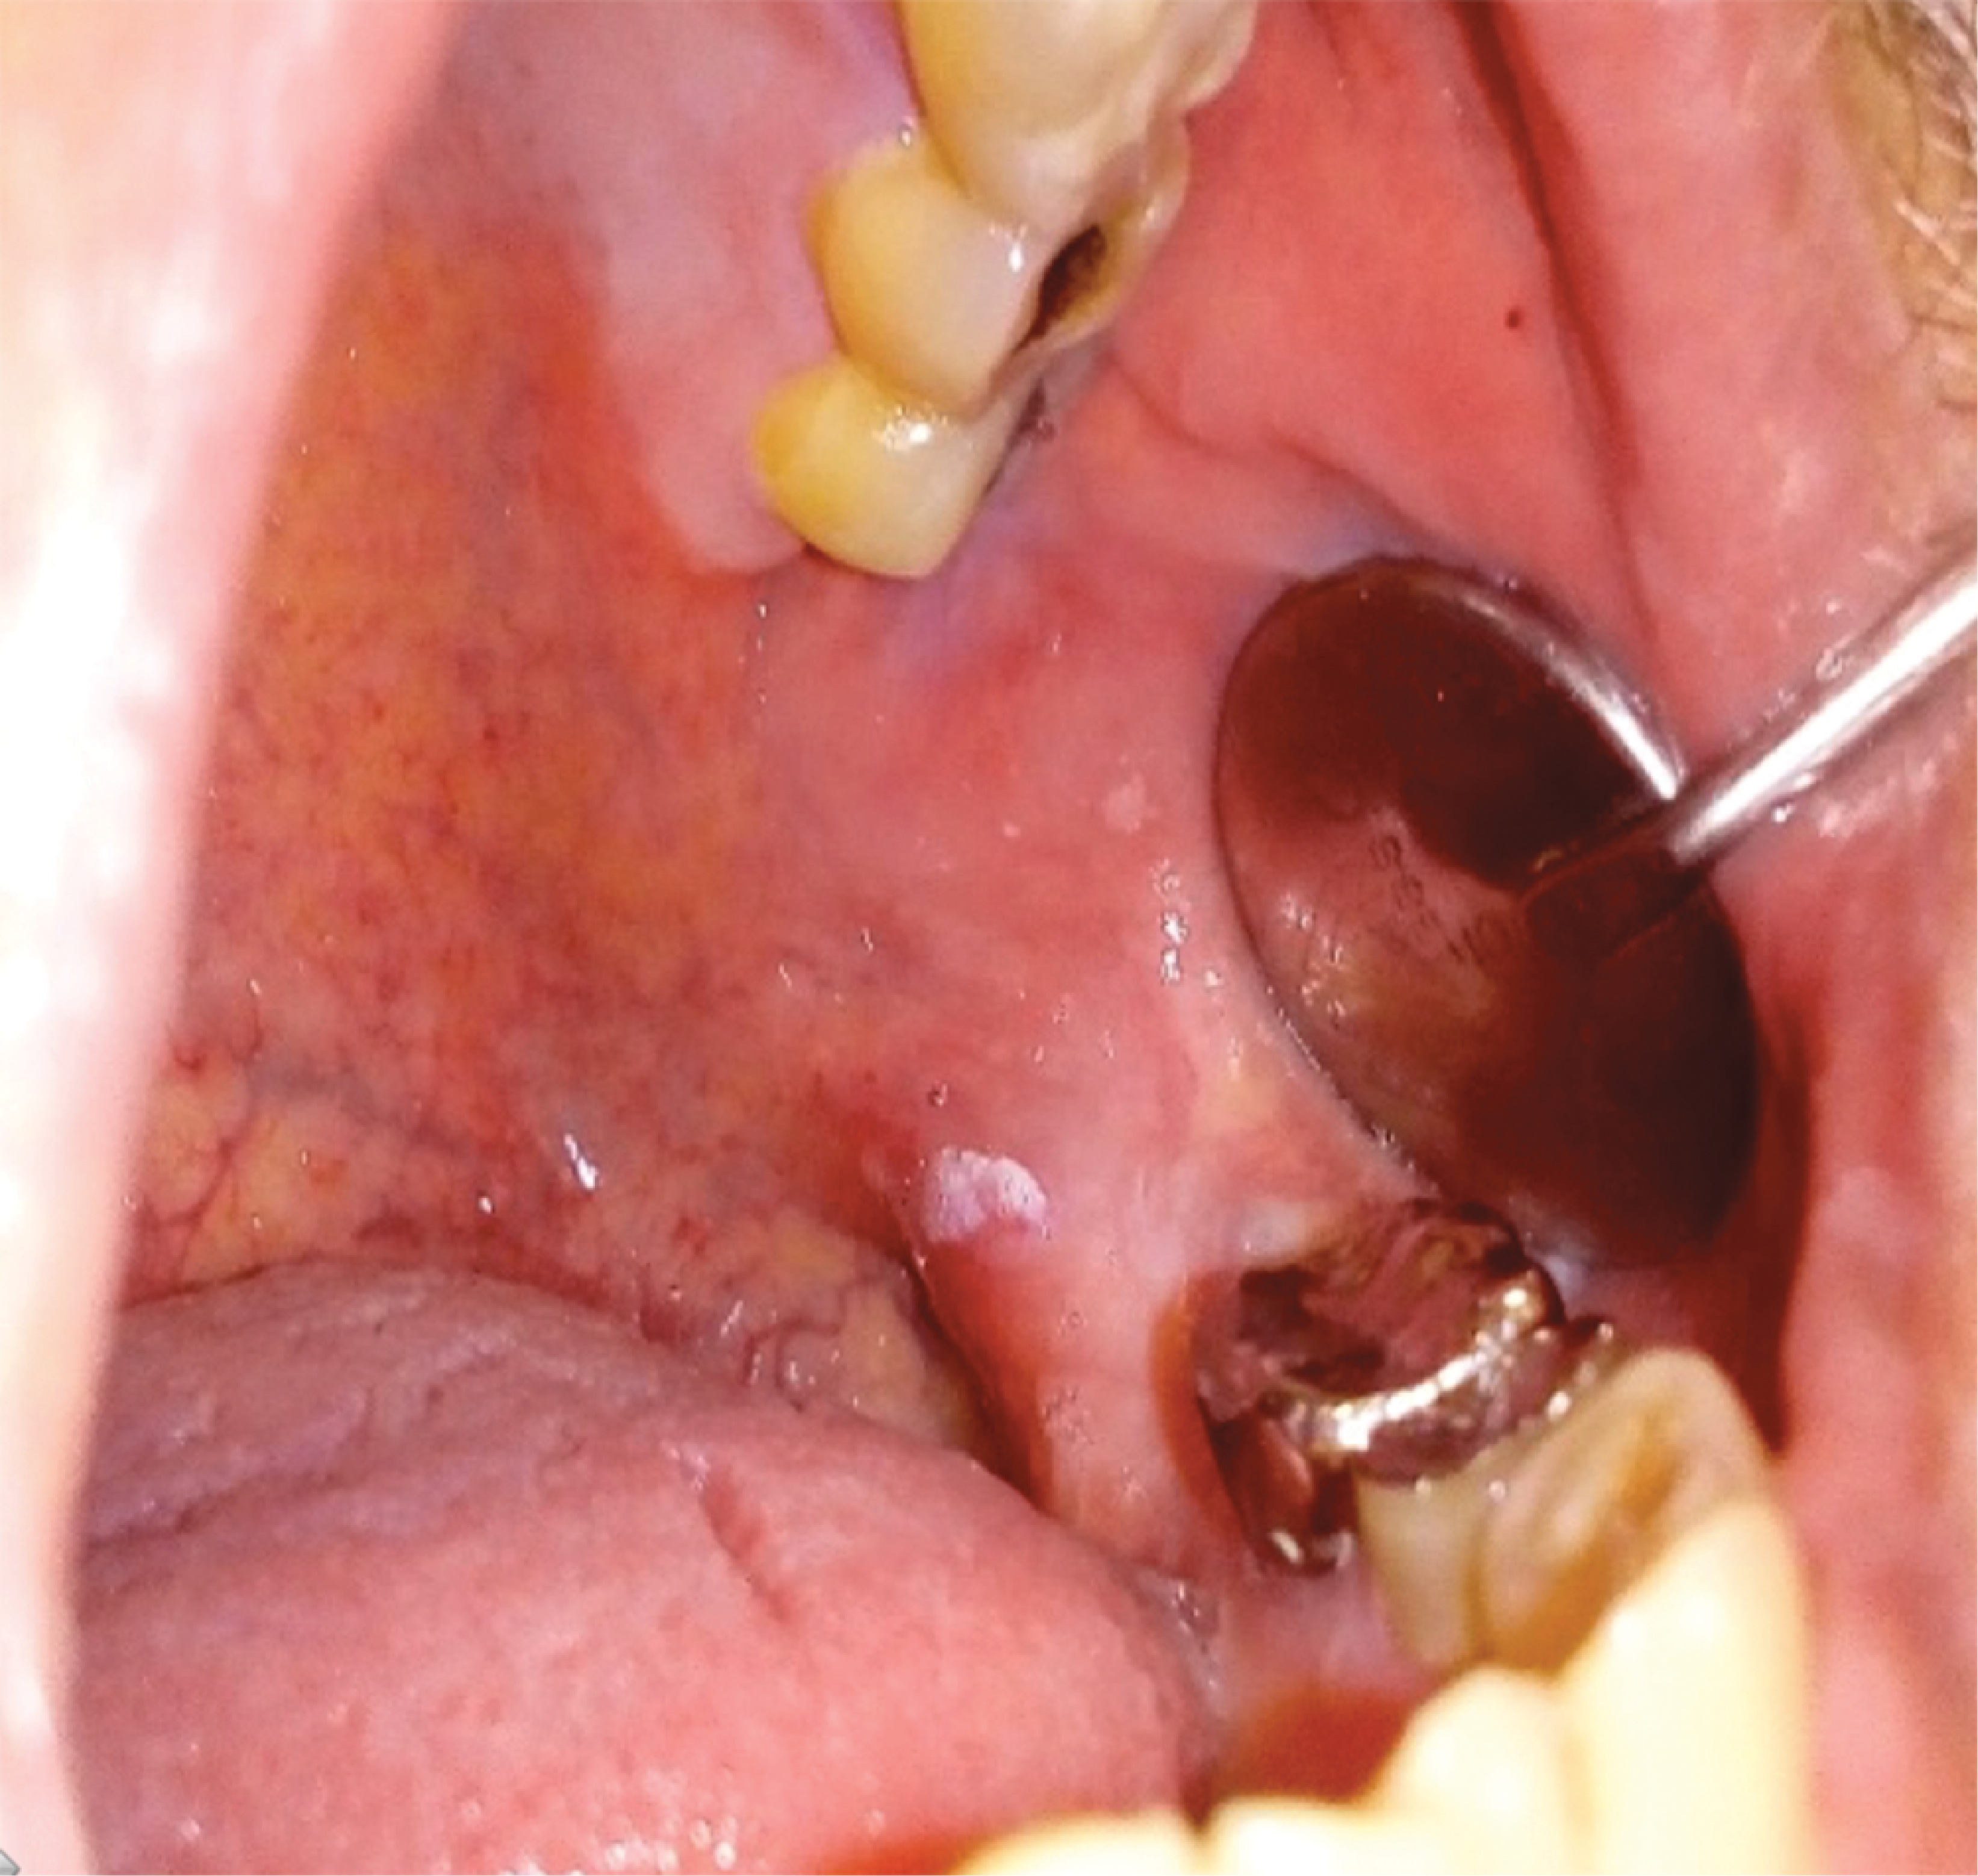

Figure 3